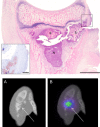

Osteomyelitis (OM) is an important cause of morbidity and sometimes mortality in children and adults. Long-term complications can be reduced when treatment is initiated in an early phase. The diagnostic gold standard is microbial examination of a biopsy and current non-invasive imaging methods are not always optimal. [111In]-leukocyte scintigraphy is recommended for peripheral OM, but is time-consuming and not recommended in children. [18F]FDG PET/CT is recommended for vertebral OM in adults, but has the disadvantage of false positive findings and a relatively high radiation exposure; the latter is a problem in children. [99mTc]-based tracers are consequently preferred in children. We, therefore, aimed to find a [99mTc]-marked tracer with high specificity and sensitivity for early detection of OM. Suppurating inflammatory lesions like OM caused by Staphylococcus aureus (S. aureus) will attract large numbers of neutrophils and macrophages. A preliminary study has shown that [99m Tc]-labelled IL8 may be a possible candidate for imaging of peripheral OM. We investigated [99mTc]IL8 scintigraphy in a juvenile pig model of peripheral OM and compared it with [18F]FDG PET/CT. The pigs were experimentally inoculated with S. aureus to induce OM and scanned one week later. We also examined leukocyte count, serum CRP and IL8, as well as performed histopathological and microbiological investigations. [ 99m Tc]IL8 was easily and relatively quickly prepared and was shown to be suitable for visualization of OM lesions in peripheral bones detecting 70% compared to a 100% sensitivity of [18F]FDG PET/CT. [ 99m Tc]IL8 is a promising candidate for detection of OM in peripheral bones in children.